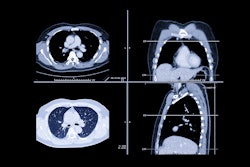

The group's retrospective study examined the prevalence of incidentally detected PE with thin-slice contrast-enhanced MDCT, and sought to determine whether the use of wide window settings might also improve detection. The group examined 589 patients (416 men and 173 women, mean age 63.4, 480 inpatients/109 outpatients) who underwent chest CT for reasons other than ruling out PE.

Twenty-five seconds following automated injection of 80 mL of contrast material (300 mg I/mL iomeprol), images were acquired on a four-detector Volume Zoom Scanner (Siemens Medical Solutions, Erlangen, Germany) at 4 x 2.5-mm collimation, table speed of 15 mm per (0.5 second) rotation, 140 kVp and 120 mAs, and reconstruction of 5-mm-thick axial slices, the authors wrote.

Two experience chest radiologists blinded to the clinical data looked for PE (a filling defect characterized by low attenuation) in the main, lobar, segmental, or subsegmental pulmonary arteries, also indicating their subjective confidence level in each diagnosis. Each dataset was examined twice, with sessions at least a week apart, once with normal window settings (width 400 H; level 40 H) and once with wide settings (width 600 H, level 100-150 H).

Good or satisfactory arterial opacification was seen in 581 of 589 (98.6%) patients evaluated, the authors found. Overall, PE was detected in 20/581 patients with analyzable scans (3.4%). Among hospital inpatients the prevalence was 4% (19/474) and 0.9% among outpatients.